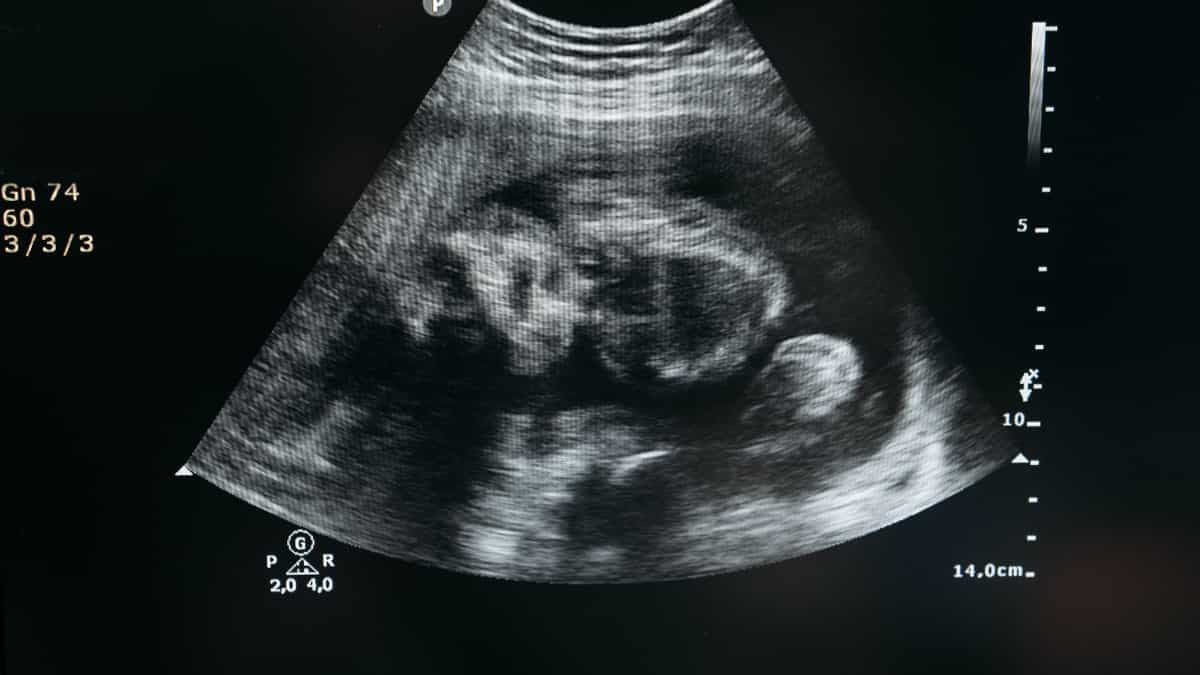

While performing balloon dilation, ultrasound was used as guidance. "We placed a needle through the mother's abdomen into the baby's heart. Then, using a balloon catheter, we opened the obstructed valve to improve blood flow. We expect and hope that the baby's heart will develop better and the heart disease will be less severe at birth," explained the senior doctor who performed the surgery.